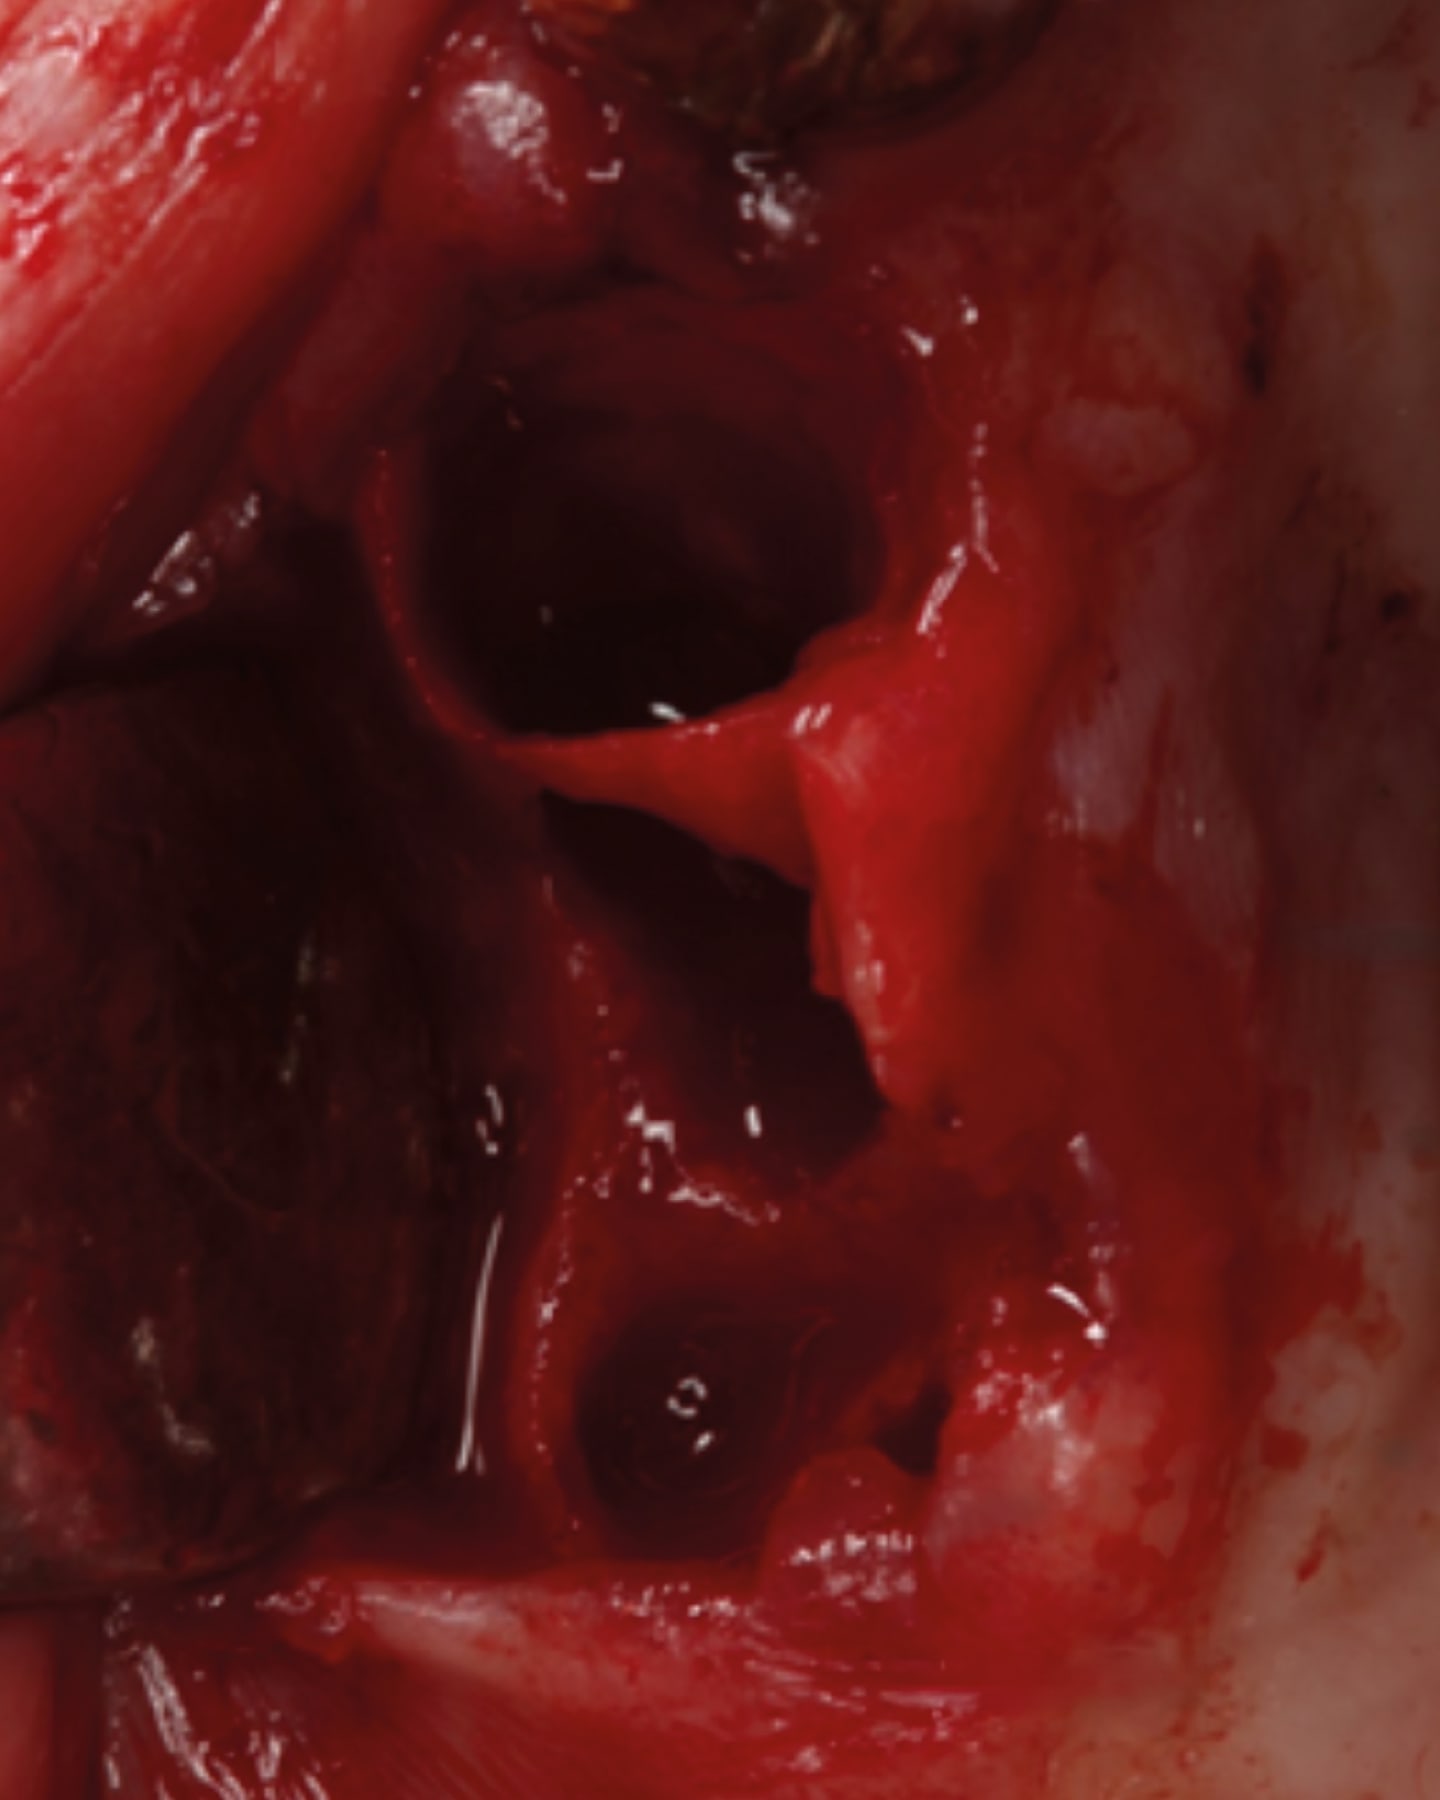

The bridge was sectioned and removed (Figure 3). The 1st molar, residual root at the 2nd premolar, canine, and central incisor were atraumatically extracted. The extraction sockets were cleaned and debrided (Figure 4). A block was fabricated from L-PRF derived from the patient’s blood and combined with cortico-cancellous bone (Maxxeus, Kettering, Ohio). The extraction sockets were filled with the graft, and edentulous areas were grafted to restore ideal volume (Figure 5). A BioXclude amnion-chorion barrier membrane (Maxxeus) was placed over the graft material, tucked under the flap margins, and the site was closed with PGA sutures (Figure 6). The patient was provided with a PTech LMHFV device and instructed to use it twice daily for the recommended 5 minutes each session and continue until returning for the post-operative appointment.